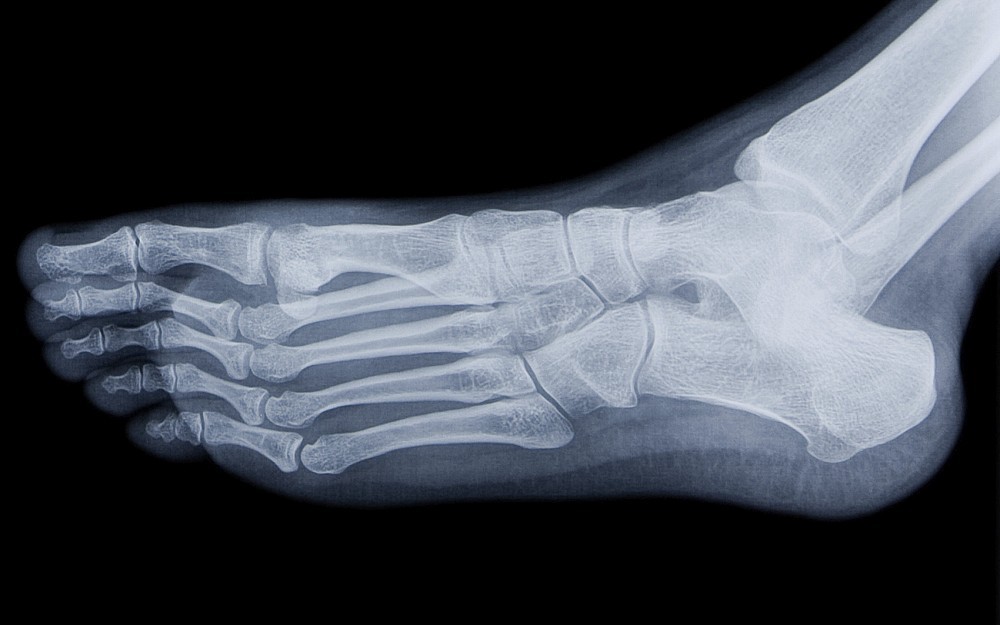

Stress fractures are more common in the lower extremities such as the shin bone, ankle and foot, and a telltale sign of a stress fracture is recurrent pain and swelling of a body part, which increases with the frequency and intensity of a particular exercise.

Often the first course of treatment for a stress fracture is to allow the body to heal itself with rest, ice and elevation. Some stress fractures; however, do not resolve themselves and require surgery.